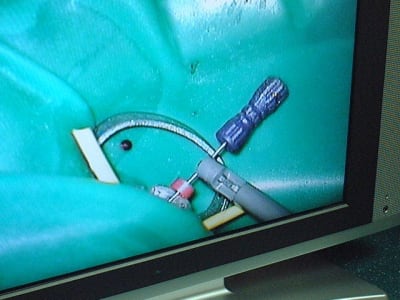

Bon repas, je digère...lui déguste endos 21/11 avec digue....

D'abord, finissons le cas du matin

photos :

L'AM, fameuse endo 11-21 avec un apex egyptien (l'apex, pas l'obturation :-( encore une patiente bien gentille...

Après, tentative endo sur une 27, ce coup ci on se fait un vrai plaisir, curetage des entrée canalaires au sonic, grossisement max... Sbire fait l'AD... bon, bref j'ai perdu bcp de temps, alors on a refermé, et sbire finira... désolé l'ami :-|

Le microscope est un outil impressionant, que je qualifierais d'outil plaisir, outil car utilité démontrée en cas de fracture canalaire, en cas de recherche du fameux mv2 (pas trouvé moi, ce matin...) mais... plaisir car on peut sûrement faire aussi bien sans... mais c'est moins rigolo et on se casse le dos.